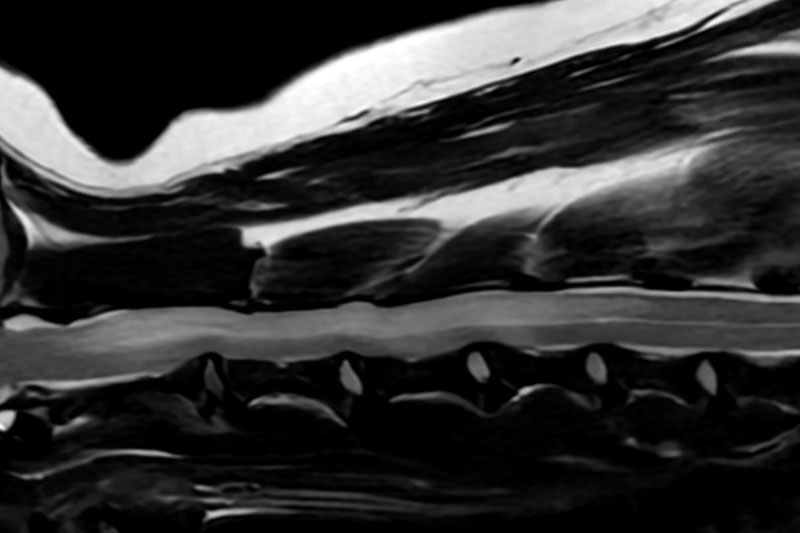

본 병원은 GE사의 1.5T 고해상도 자기공명영상장치(MRI)를 이용하여, 자기장을 이용한 비침습적 방식으로 뇌, 척수, 근골격계 등 다양한 연부조직을 정밀하게 영상화할 수 있습니다. MRI는 방사선을 사용하지 않아 반복 촬영에도 안전하며, 신경계 및 연부조직에 대한 탁월한 해상도를 제공하여 정확한 진단에 매우 유용합니다.

또한 본원의 MRI 장비는 GE사의 PROPELLER 기법을 도입하여 호흡이나 움직임에 따른 영상 왜곡을 최소화하면서도 검사 시간을 단축시켜, AI 기반 영상 처리 기술을 통해 노이즈를 줄이고 더욱 선명하고 명확한 영상을 획득할 수 있습니다. 이러한 기술적 강점을 바탕으로 마취 시간과 그에 따른 환자의 부담을 줄이면서도, 진단에 충분한 고화질 영상을 안정적으로 확보할 수 있습니다.

| 척수/신경계 | 디스크 탈출, 척수압박, 척수염, 척수종양 등 |